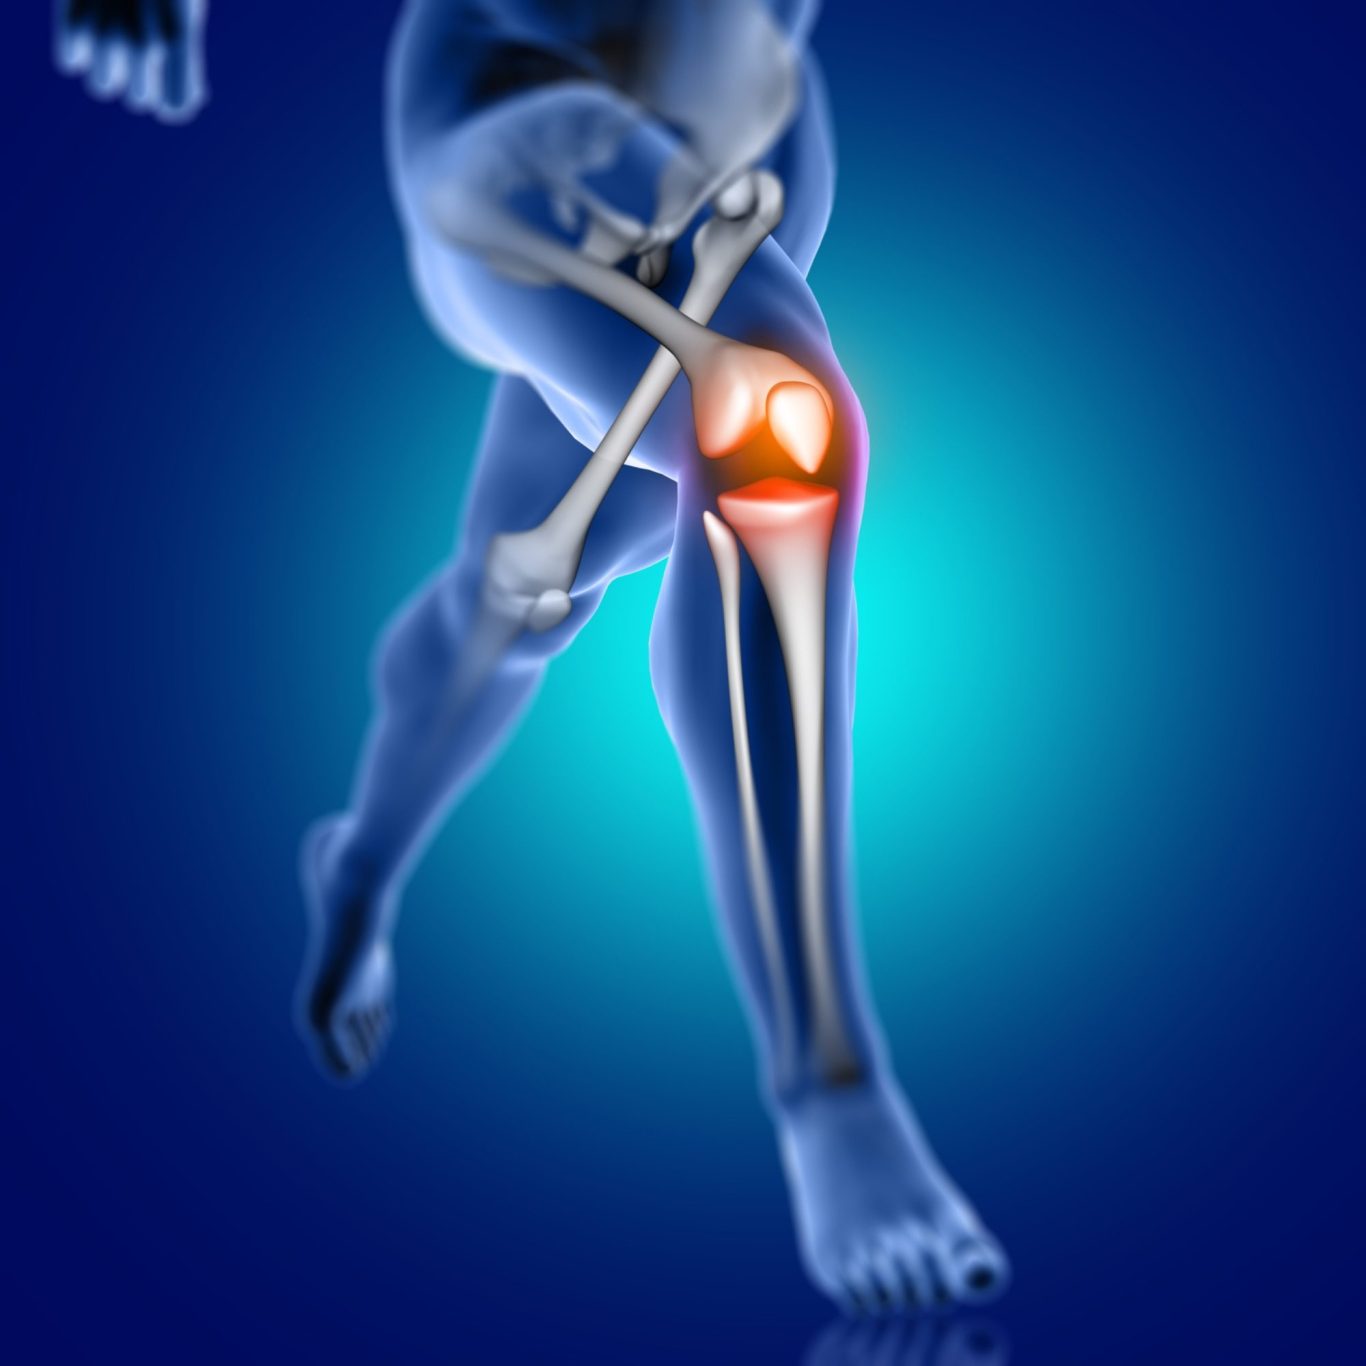

Arthrosetherapie

Weil jedes Gelenk zählt – innovative Hilfe für weniger Schmerz und mehr Lebensfreude.